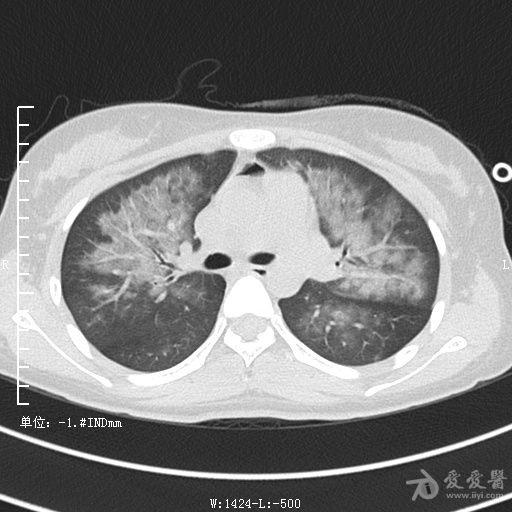

典型支气管扩张及肺水肿CT片

典型支气管扩张肺水肿